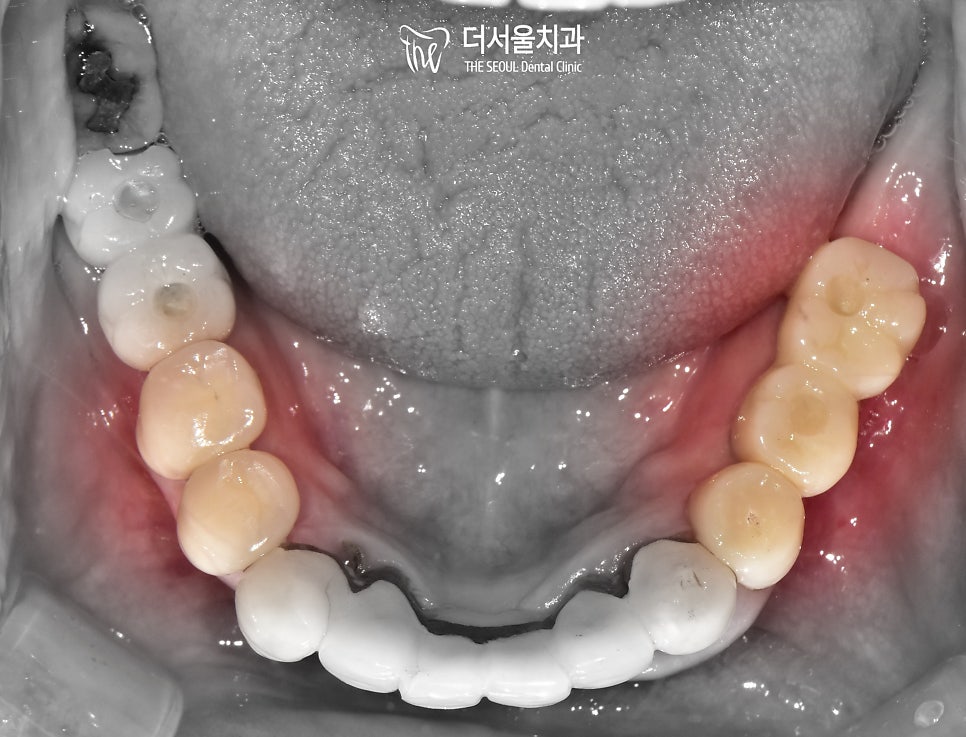

이후 크라운 제작을 통해

문제가 생겼던 곳들을 모두 개선했습니다.

원하던 대로 좋은 결과를 얻을 수 있었는데요.

통증이 느껴졌던 오래된 브릿지가

튼튼하고 심미성이 좋은 지르코니아로

바뀌어 있는 모습을 확인할 수 있습니다.

교합도 잘 맞물리고 있었으며

크라운도 인접치 형태에 맞춰

조화롭게 제작이 되었습니다.